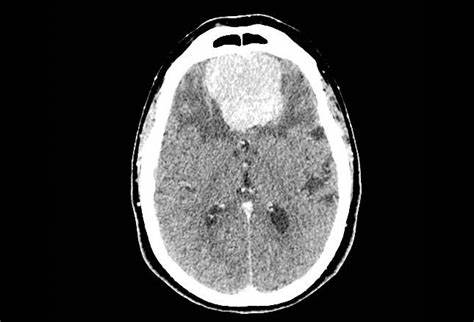

沒有任何癥狀的腦膜瘤需要手術(shù)嗎?腦膜瘤治療必知

腦膜瘤是中樞神經(jīng)系統(tǒng)較常見的原發(fā)腫瘤,腦膜瘤,在很多方面,就是是神經(jīng)外科的靈魂。腦膜瘤治療上的進(jìn)步,其實(shí)就反應(yīng)了整個(gè)神經(jīng)外科的進(jìn)步。而同時(shí),神經(jīng)外科方面的每一個(gè)進(jìn)步,都會被應(yīng)用于腦膜瘤的治療。1922年,神經(jīng)外科之父哈維·庫欣在他的卡文迪什演講中報(bào)告了85例腦膜瘤病例。同年,庫欣寫道:“迄今為止,在整個(gè)外科領(lǐng)域,沒有什么比成功切除腦膜瘤并隨后恢復(fù)功能更令人滿意的了。”將近100年后,這些話仍然適用。盡管腦膜瘤被認(rèn)為是一種良性疾病,但它的出現(xiàn)與局灶性神經(jīng)缺陷、癲癇發(fā)作和生活質(zhì)量下降有關(guān)。如今的腦膜瘤手術(shù)和神經(jīng)外科先驅(qū)Harvey Cushing那個(gè)時(shí)代相比已經(jīng)完全不可同日而語。腦膜瘤治療又有什么突破?

腦膜瘤和其他中樞神經(jīng)系統(tǒng)腫瘤一樣,取決于其位置。腦膜瘤可見于任何顱內(nèi)或脊膜表面。很少,腦室內(nèi)腦膜瘤被發(fā)現(xiàn)。腦膜瘤通常不是快速生長或浸潤性病變,有隱匿的癥狀。許多是在大腦成像中偶然發(fā)現(xiàn)的。雖然沒有腦膜瘤的病理學(xué)表現(xiàn),但典型的臨床癥狀是顱內(nèi)壓升高、局灶性神經(jīng)(包括顱神經(jīng))缺損或局灶性腫塊效應(yīng)引起的全身性和部分性癲癇發(fā)作。人格改變、意識混亂和意識水平改變,是在前(額)或矢狀竇旁腦膜瘤中,較初可能被誤診為癡呆或抑郁癥。有這種癥狀的病人的鑒別診斷相當(dāng)廣泛,應(yīng)該包括其他顱內(nèi)病變(如膠質(zhì)瘤或轉(zhuǎn)移瘤)。